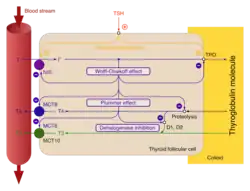

Beim gesunden Menschen gibt die Schilddrüse bedarfsgerecht die Schilddrüsenhormone – Thyroxin (T4) und Triiodthyronin (T3) – ins Blut ab. Die Produktion dieser Hormone wird durch den thyreotropen Regelkreis gesteuert. In der Schilddrüse bewirkt das in der Hirnanhangsdrüse (Hypophyse) gebildete Hormon Thyreotropin (TSH) eine gesteigerte Produktion der Schilddrüsenhormone und übt zusätzlich einen Wachstumsreiz auf das Schilddrüsengewebe aus.

Zum Aufbau von Thyroxin und Trijodthyronin benötigt die Schilddrüse Jod. Der Jodbedarf des Erwachsenen liegt bei etwa 200 μg pro Tag. Eine ausreichende Jodzufuhr ist durch jodiertes Speisesalz in Deutschland im Allgemeinen gewährleistet. Die Jodversorgung der Bevölkerung Deutschlands wurde 2004 von der Weltgesundheitsorganisation (WHO) aufgrund der durchschnittlichen Jodausscheidung im Urin als „optimal“ bezeichnet.[19] Die Menge der produzierten Hormone schwankt innerhalb der Gruppe schilddrüsengesunder Personen (Normalpopulation) erheblich, das heißt, dass der Referenzbereich der laborchemischen Ergebnisse relativ groß ist. Die Schwankungen bei Messungen bei derselben Person sind wesentlich geringer.[20] Die aus der Schilddrüse ins Blut abgegebenen Schilddrüsenhormone (T3 und T4) werden dort größtenteils an unterschiedliche Proteine (hauptsächlich TBG, TBPA und Albumin) gebunden und dabei biologisch inaktiv. Nur etwa 1 ‰ der im Blut befindlichen Schilddrüsenhormone zirkuliert frei (fT3 und fT4). Die Schilddrüsenhormone steigern den Grundumsatz, die Empfindlichkeit des Herzens für Katecholamine, den Calcium- und den Phosphatumsatz sowie die Erregbarkeit von Muskel- und Nervenzellen und hemmen die Protein- und die Glykogenneubildung.

Die Jodaufnahme der Schilddrüse ist nicht nur vom TSH-Spiegel abhängig, sondern unterliegt auch einer jodabhängigen Autoregulation. Gaben großer Mengen von Jodid (mehrere hundert Milligramm – der Tagesbedarf des Gesunden wird von der WHO mit 200 Mikrogramm angegeben) hemmen Jodidaufnahme und Hormonsynthese (Wolff-Chaikoff-Effekt, nach Louis Wolff, 1898–1972, US-amerikanischer Kardiologe und Israel Lyon Chaikoff, US-amerikanischer Physiologe[39]) sowie die Mobilisierung von Schilddrüsenhormonen aus Thyreoglobulin und deren Freisetzung aus den Thyreozyten in die Blutbahn (Plummer-Effekt, benannt nach dem US-amerikanischen Internisten und Endokrinologen Henry Stanley Plummer, 1874–1936). Diese beiden Effekte, die jeweils nur wenige Tage anhalten, machte man sich früher zur Behandlung einer Hyperthyreose vor Schilddrüsenoperation zunutze („Plummern“).[40][41]